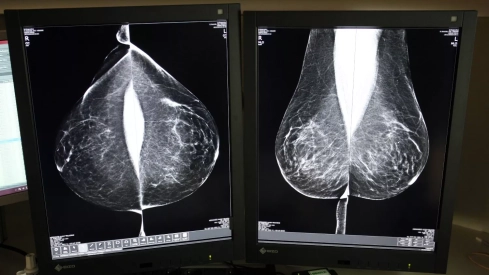

Desde su puesta en marcha en 1992, el programa se basa en el sistema de doble lectura, un protocolo que establece que cada mamografía sea evaluada por al menos dos radiólogos, de forma independiente, aumentando así la fiabilidad de los diagnósticos. Sin embargo, aumenta la carga de trabajo y plazos, motivo por el cual Sacyl ha optado, de nuevo, por externalizar el servicio al que el año pasado dedicó casi cuatro millones.

Servicio de Mamografía del Hospital Río Hortega de Valladolid